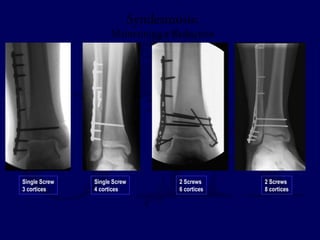

Syndesmosis:

Maintaining a Reduction

Single Screw

3 cortices

4 cortices

2 Screws

6 cortices

8 cortices

3.5 mm vs 4.5 mm screw(s)

3 cortices vs 4 cortices

Retain vs Removal

Metallic vs Bioabsorbable

NO CONSENSUS